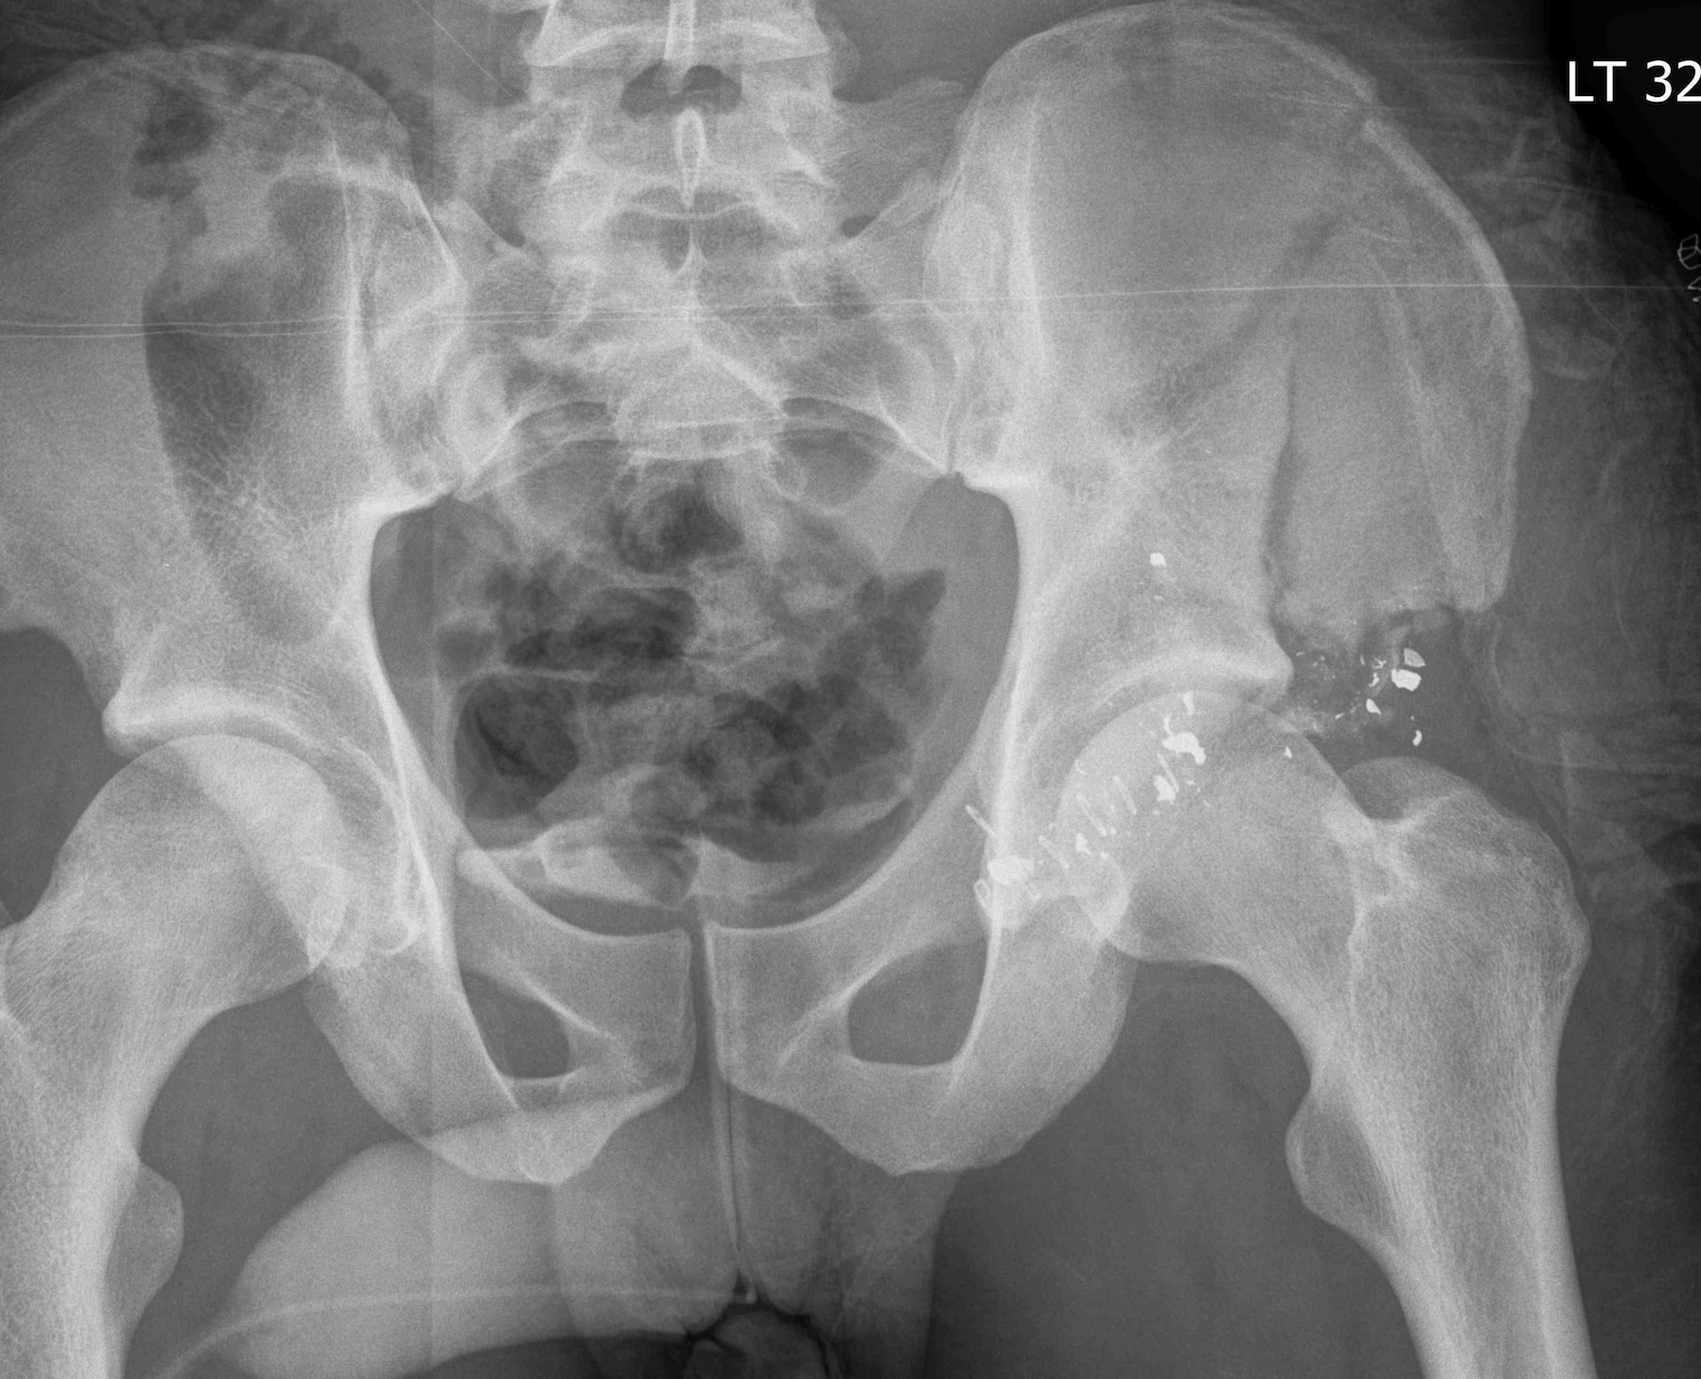

Gunshot Wound Compound Pelvic Fracture

First OT

- scrub

- large incisions to explore wound

- excise all devitalised tissue

- washout +++

- skeletal stabilisation

- always leave wound open